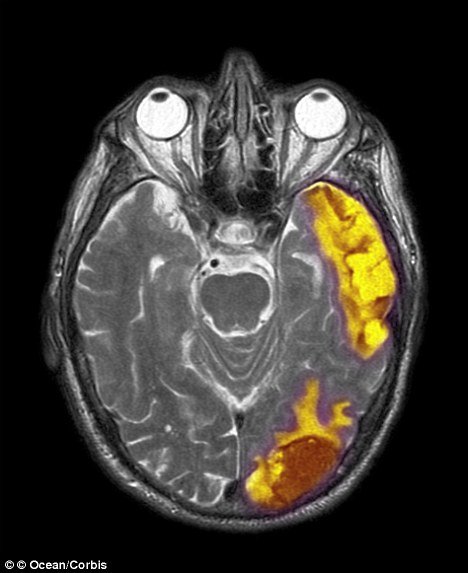

In the most recent study, Prof. Brick Johnstone studied 20 people with traumatic brain injuries affecting the right parietal lobe, the area of the brain situated a few inches above the right ear.

Prof. Brick Johnstone found that the participants with more significant injury to their right parietal lobe showed an increased feeling of closeness to a higher power.

“Neuropsychology researchers consistently have shown that impairment on the right side of the brain decreases one’s focus on the self,” he said.

Prof. Brick Johnstone says the right side of the brain is associated with self-orientation, whereas the left side is associated with how individuals relate to others.